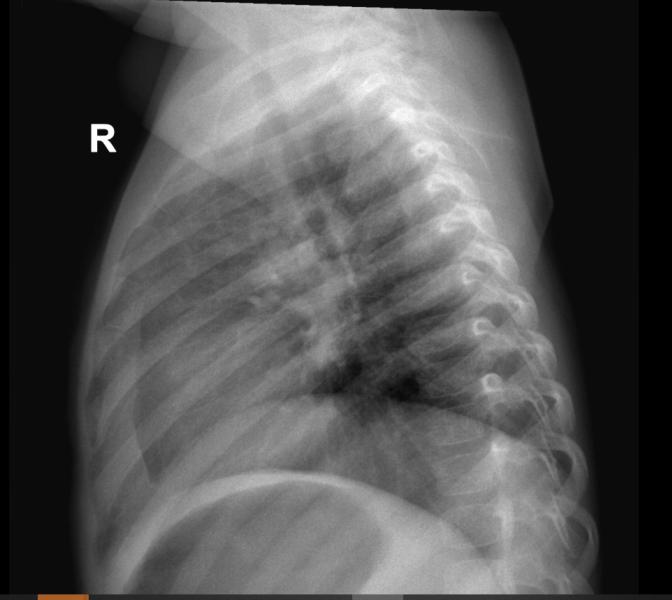

Рентгенологи, нужна помощь! Что видите на снимке? Описание, подозрения и ваши заключения.

post image 1

Есть тут специалисты - рентгенологи?⁉️ Кто видит что?!